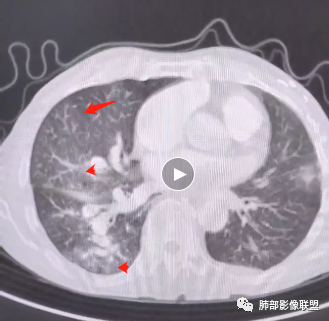

老年男性,胸闷、浮肿10天,左肺尖可见肺大泡影,两肺散在纤维索条影,右肺见弥漫性腺泡结节,以右肺上叶为著,右肺下叶局部小叶间隔增厚,双侧胸腔、右侧叶间裂及心包积液,结合实验室及影像检查,符合心衰及肺水肿表现,右肺部病变符合PVOD表现。

双肺透过度不均匀,右肺减低,可见腺泡结节影,中央间质、周围间质增厚,少量积液。肾衰病史首先考虑肾性肺水肿。

2.右肺广泛密度增高、腺泡结节样磨玻璃影,血管影明显扩张,小叶间隔增厚。

3.右肺下叶纤维钙化灶。

4.左肺相对广泛低密度、血管纤细(显著)。

5.双侧胸腔少量积液,右侧较为明显。